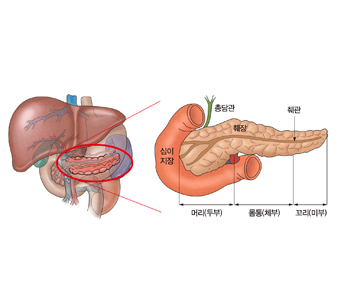

위치췌장의 앞으로는 횡행결장과 위가, 아래쪽으로는 소장과 인접해있습니다. 췌장의 머리부위에는 하대정맥과 복부대동맥과 인접하며 몸통은 상장간막동맥, 상장간막정맥과 인접하며 꼬리부위는 좌측신장과 비장과 인접해있습니다.

췌장은 약 15cm, 무게는 약 100g 정도로 가늘고 긴 모양이며 머리, 몸통, 꼬리의 3부분으로 나눌 수 있습니다.

또한 췌장의 위치가 후복막이고 주변에 혈관이 많이 존재해 진단 당시 이미 전이가 되어있을 가능성도 많습니다. 그러나 췌장암 중 머리쪽에 생긴 암은 황달이 나타날 수 있으므로 체부나 꼬리부분에 생긴 것보다는 빨리 발견될 수는 있습니다.